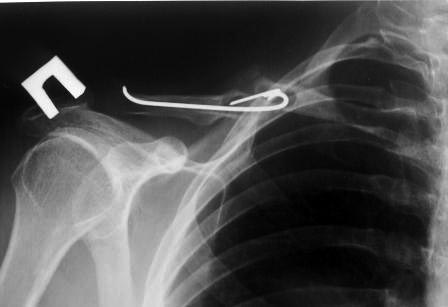

В заключение, только 25% изолированных переломов ключицы, леченных консервативным методом не срастаются, а из них 1/3 симптоматические. Болезненные ложные суставы надо оперировать, и здесь представлен случай свежего болезненного ложного сустава, оперированного через 4 месяца.

Освобожден средний фрагмент и боковая компрессия лагированием, фиксация пластиной..